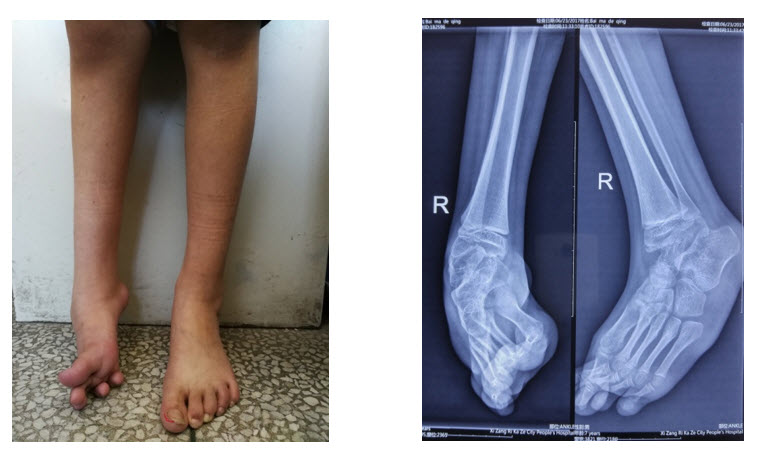

圖1:患兒站立位照 圖2:術(shù)前患足X片(右足高弓馬蹄內(nèi)翻畸形)

患兒為來(lái)自日喀則市崗巴縣的7歲藏族女孩,出生后發(fā)現(xiàn)右腳呈內(nèi)翻畸形,1歲時(shí)畸形加重,不能正常走路,在當(dāng)?shù)蒯t(yī)院做了跟腱延長(zhǎng)術(shù),但隨著年齡增長(zhǎng),畸形加重跛行更為明顯,行走時(shí)腳痛嚴(yán)重。在幾乎絕望之時(shí),患兒家長(zhǎng)找到了日喀則市人民醫(yī)院骨科援藏專(zhuān)家施忠民主任。已經(jīng)圓滿(mǎn)完成了一年援藏工作即將啟程回上海的施主任,看著小女孩因畸形導(dǎo)致殘疾的腳和家長(zhǎng)憂(yōu)心的眼神,決定為小女孩做手術(shù),小女孩和其父母的臉上露出了久違的希望的笑容。